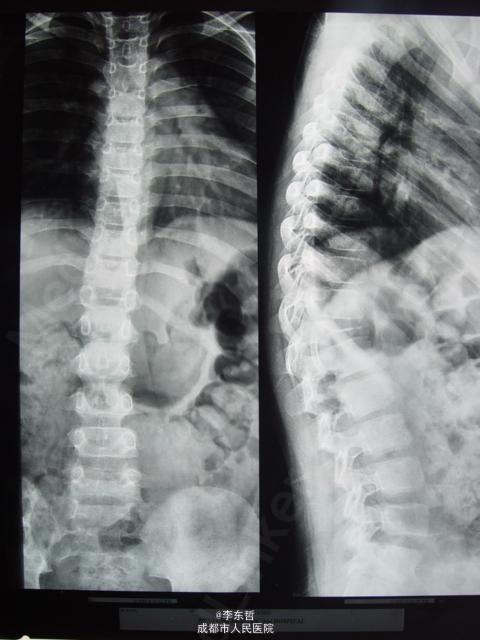

胸椎X光,颈椎x光